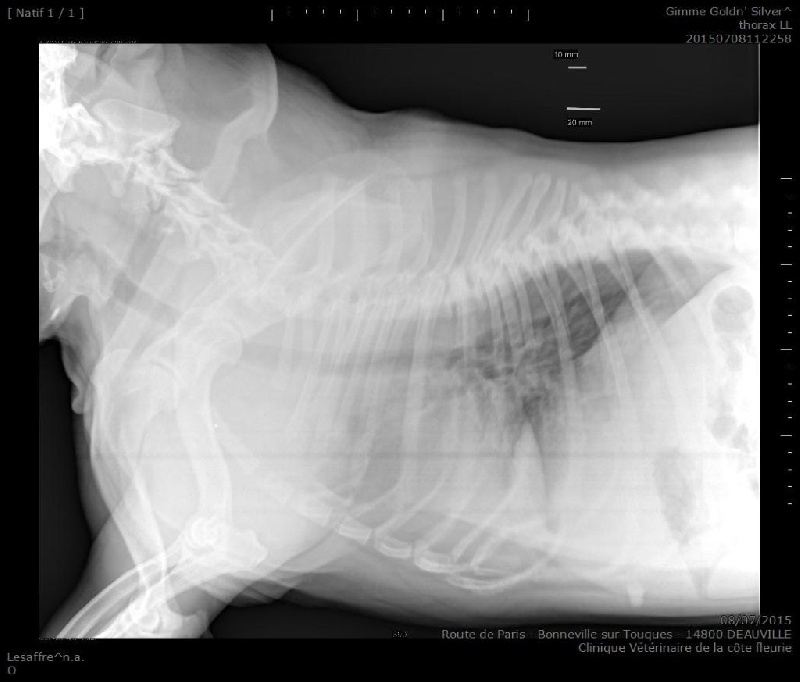

Radio trachée OK

écho-doppler cardiaque : OK ( indemne sténose pulmonaire et autre cardiopathie congénitale ) test validé CBA

HUU ( hyperuricosurie ) : N/N  ( homozygote normal , exempt ) Luxation rotules / examen postérieurs et grassets ( validé CBA ) : 0/0 idemne NM ( luxation glande nictitante ) : 0/0 radio trachée : OK écho-doppler / examen cardiaque ( validé CBA ) : idemne sténose pulmonaire ou autre cardiopathie congénitale  |